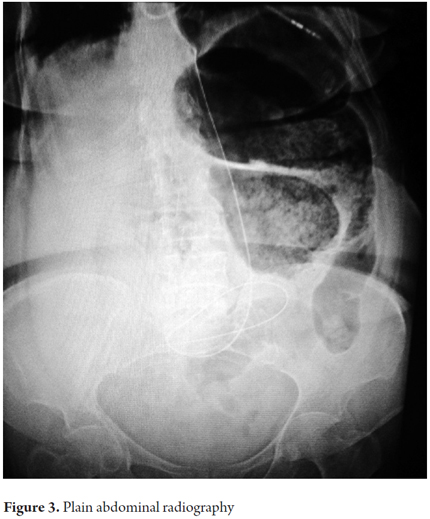

Her blood tests were normal. Her BUN was 89 and arterial gases showed severe metabolic acidosis (pH 7.31) with hyperlactatemia (11mg / dl). An abdominal x-ray showed distended colonic loops with air-fluid levels but no observable distal gas (Figure 3).

Diagnoses are not normally made prior to surgery since the radiographic findings are nonspecific unlike the typical coffee bean image of sigmoid colon volvulus. (4, 8) Some authors mention that a distended colon with two air-fluid levels in the epigastric region or the presence of a handle shaped U in the left upper quadrant in abdominal radiography may suggest the diagnosis, but this is not consistent. (5, 11, 12) As for CT scans, a review by Vandendries et al. reports no typical radiological characteristics for transverse colon volvulus. (9)